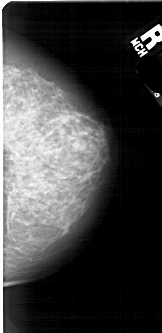

A_1883_1.RIGHT_MLO

RIGHT_MLO LINES 5266 PIXELS_PER_LINE 2671 BITS_PER_PIXEL 12 RESOLUTION 43.5 NON_OVERLAY